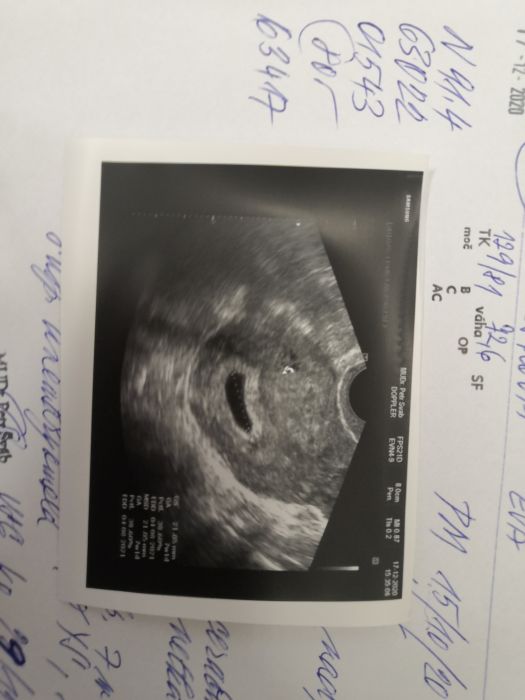

Ahoj, gratuluji Katie ke 2//,a všem na které 2 //vykoukly a přeji hodně štěstí všem které se snažíte. U mě je to takové zamotané, poslední MS jsem měla 15.10. V listopadu nic, tak jsem si dělala 30.11.test a za 3 dny znova a byly negativní, říkala jsem si, že to může být tím, že kojím, mám 6. měsíční holčičku, na netu to také psali, že když se kojí, tak MS se může ztratit, ale v prosinci 13.12.mi mužský říká, že jsem nějaká jiná, koupil mi test a ještě ten den odpoledne na mě vykoukly 2//, žádný dušík, ale silné //, 17.12. jsem byla u dr a ten mi řekl, že velikostně je to 7 týden, ale bohužel se jedná zřejmě o neprosperujici těhu, protože byl vidět jen úplně prázdný gestační váček, ale objednal měna29.12.a tam, už bylo něcojako plod a hlavně bylo slyšet srdíčko, dr mi vysvětlil, že jsem asi otěhotnělapozději teďjdu na kontrolu 1 8.1.tak jsem zvědavá co mi řekne?

Ahoj, tak dnešní kontrola u dr

, vše v pořádku a 11+1tt.